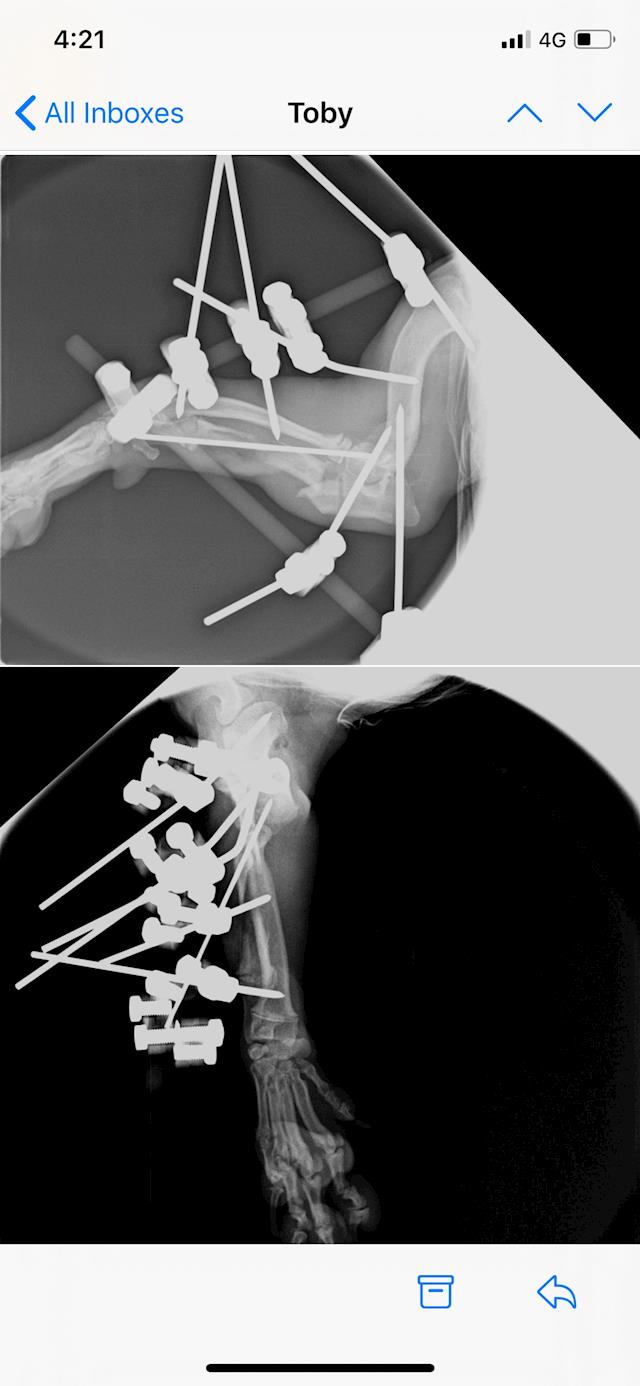

Well we are now at week 3 after Toby’s surgery. Last week after xrays it was discovered that his growth plate had cracked. So a plan was put in place to remove the pins from his leg this week. Pins came out Monday and he’s been back

At vets all day today managing the pain. The hope now is that the elbow and ulna that was rotated will stay in place with no pins in place to hold it so fingers crossed. Day one no pins and X-ray shows everything is where it should be!!! Toby has started physio and is enjoying all the massages that he is getting!!! See the new photos

Toby came through his 4.5 hour surgery on 29 October. His Ulner had to be broken in 2 places to get it aligned and then all pinned into place. See photos. He has to keep the frame on for 1 month with weekly X-rays to check it is still in place.